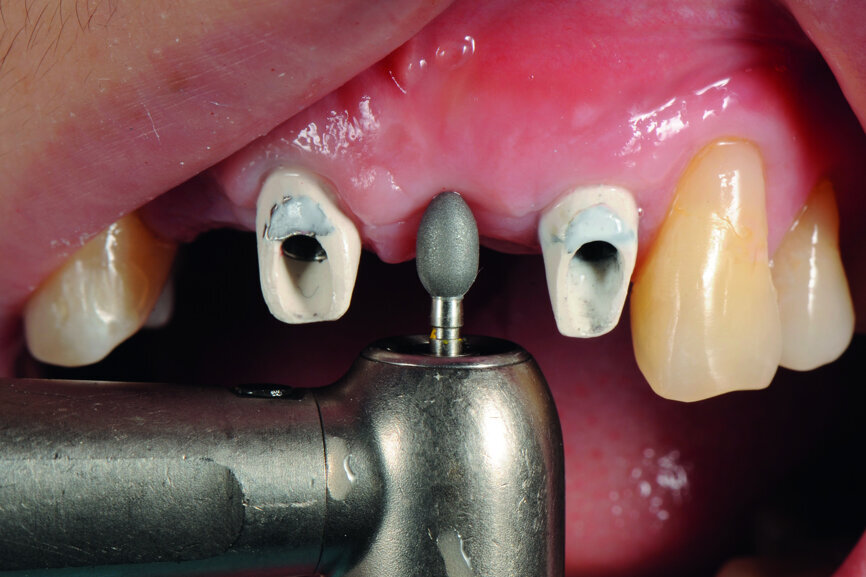

Fig. 16: Modification of the gingival contour under the pontic.

Fig. 17: Finishing of the reshaping of the gingiva.

Teeth #12, 21 and 22 were extracted. Tooth #11 underwent early implantation and tooth #22 immediate implantation with GBR (Figs. 5 & 6). After three months of healing, osseointegration had taken place. An implant level impression was taken for fabricating a provisional bridge supported by temporary abutments for teeth #12–22. The technician modified the shape of the artificial gingiva on the model in order to form the proper gingival curve and emergence profile, then finished the provisional bridge, while the dentist modified the gingival shape using an olive-shaped bur intraorally (Figs. 7–18).

In this case, we followed the second option. After using an olive-shaped bur to adjust the form of the gingiva under the pontic, making it match the provisional restoration, which had already been well designed and manufactured, a perfect soft-tissue outcome was achieved.